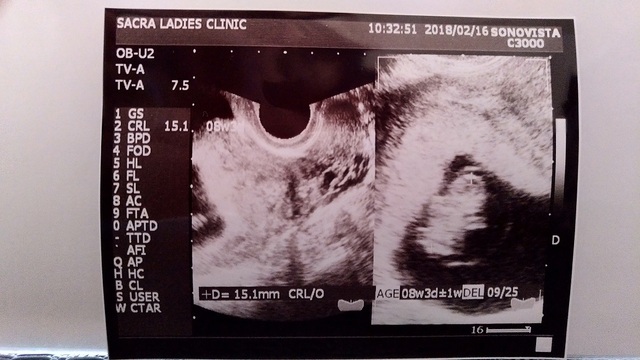

8週1日(8w1d・女の子)|やまやま06 さん(27歳)

エコー写真撮影時のエピソード:

2回目の健診でのエコー。

無事に育っているか不安でしたが形が少し出来てきていて、成長してくれているんだなと実感。悪阻はほとんどなく過ごせていました。

義理の両親にもこの時くらいに報告。 すごく喜んでくれ、私の体調も気にかけてくれるようになりました。